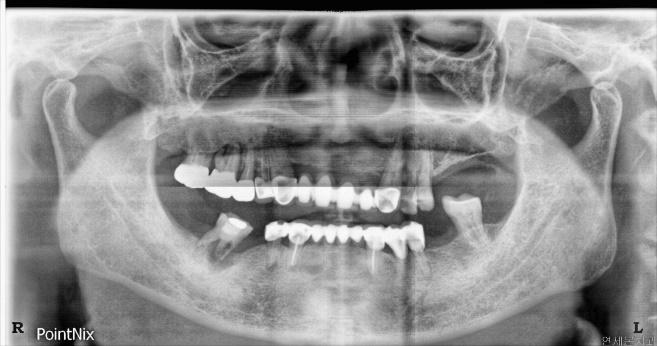

VAKA Ⅰ. Mandibular posterior bölgede temiz implant 11,4 yıl F/UFig. 1. Ameliyat öncesi panorama. 37 yaşında bir erkek hasta, kırık kök desteği ekstraksiyonu ve implant cerrahis...